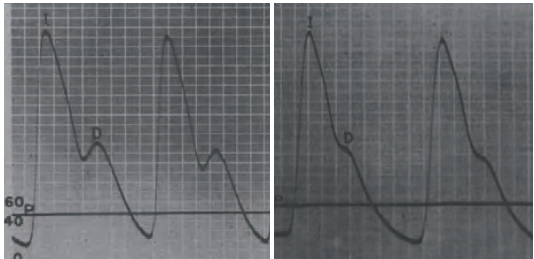

前边我们提到,脉搏波的速度、波形等信息,依赖于血管和血液的力学性质。那一个很自然的想法是,脉搏波的性质,岂不是可以很好地反映人体的健康情况!是这样!心脑血管疾病作为人类头号杀手(远超癌症),给人类健康造成了极大威胁。而脉搏波一定程度上可以反映血管的健康信息[2],比如:

正常人和发生动脉硬化的脉搏波对比图 | 图自[7]

通过测量不同位置的脉搏波压力变化图,可以反映血管的健康状况 | 图自[8]